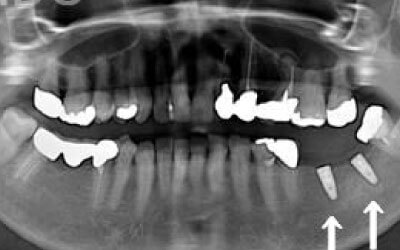

しばらくすると、抜けたままでも慣れてしまうことがありますが、その後に大きな問題が生じることがあります。

1 周囲の歯が早く抜ける

抜けた歯にかかるはずだった噛む力が、知らず知らずのうちに他の歯に負担をかけてしまいます。その結果、残っている歯が突然折れてしまい、抜歯が必要になることがよくあります。

2 歯が傾いてくる、落ちてくる

歯は互いに支え合い、バランスを保っています。そのため、歯が抜けると支えがなくなり、抜けた部分の両隣の歯が傾いたり、上の歯が下に移動してきたりすることがあります。